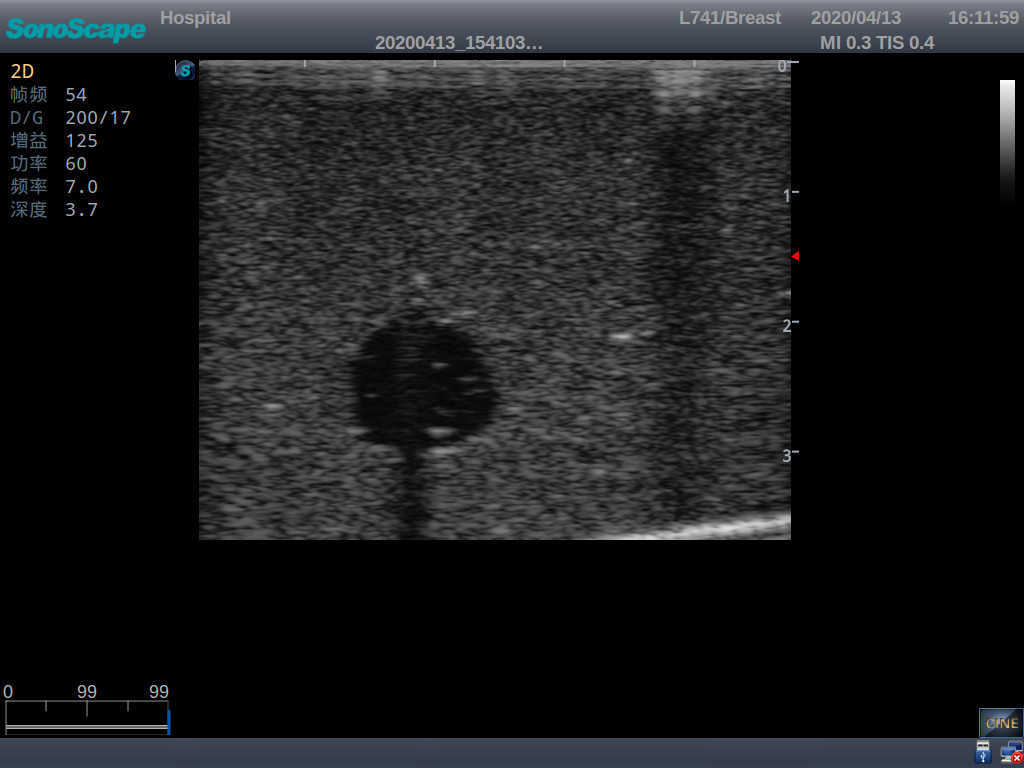

The Wearable Breast Ultrasound Examination Model allows users to develop and practice the skills necessary to gain proficiency in breast palpation, using ultrasound for normal and abnormal imaging and biopsy. It simulates adult female breasts with realistic size and appearance.

2)  Each model contains 8 space-occupying lesions of varying sizes, different in touch, elasticity and ultrasonogram

4) Biomimetic material allowing users to see clear and real normal tissues and space-occupying lesions that are hyperechoic, hypoechoic and isoechoic as they would see in the clinical environment